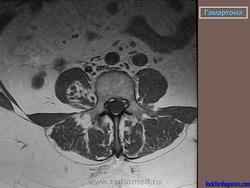

Гамартома

Приложения:

1.gam_.6_250.jpg2.gam_.9_116.jpg3.gam_.10_100.jpg1.gam_.7_169.jpg2.gam_.8_149.jpg